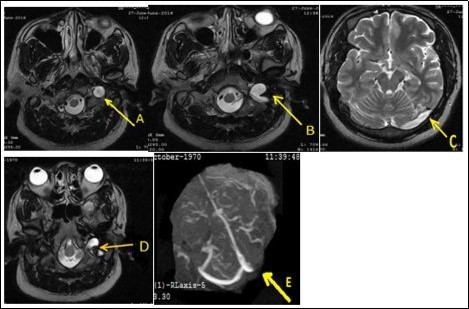

A 46-year-old man was admitted in neurology on June 27, 2016 for left occipito-temporal headache progressively for 2 weeks associated sometimes with nausea and rarely vomiting. He underwent a physical examination of an ophthalmologist and then by a physician of Otorhinolaryngology who had not diagnosed any pathology. On admission, somatic examination was normal. Routine biologic test were normal kidney, hepatic, ionogram, blood count were normal, sedimentation rate was 22 mm /h and C-reactive protein was less normal). The activated cephalin time and the plasmatic homocysteinemia were normal. The activity of protein S and the activated protein C were normal. The chest X-ray and electrocardiogram were normal. The brain ct-scan suspected a left transverse sinus thrombosis. Venous magnetic resonance angiography displayed a left internal jugular vein thrombosis extended to the left transverse sinus associated with a left ethmoidal sinusitis (Figure 1). The cervical doppler was normal. Treatment with low molecular weight heparin was initiated and then replaced with antivitamins K to achieve an international normalized ratio (INR) between 2 and 3 in addition to ofloxacin for 2 weeks and paracetamol. After three months, its remains a partiel jugular thrombosis with persistance of complete transverse sinus thrombosis.

Figure 1.Thrombosis of the left internal jugular vein extended to the transverse sinus (A, B, C). After three months of anticoagulant therapy, it remains a partial thrombosis of the jugular vein (D) and complete thrombosis of the transverse sinus (E).